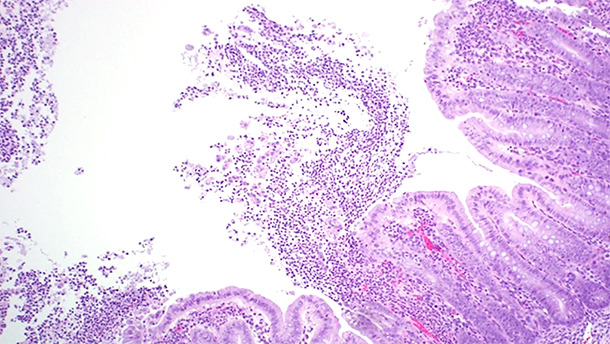

Las lesiones asociadas a la ICD se concentran básicamente en el intestino grueso. El edema de mesocolon (figura 1) es la lesión macroscópica clásica que se observa en los casos de ICD. Sin embargo esta lesión no es patognomónica; Yaeger et al demostraron que el edema de mesocolon en lechones no es un buen predictor de toxinas por C. difficile (Yaeger et al., 2007). El examen histopatológico de los animales afectados reveló una colitis ulcerativa fibrinopurulenta multifocal o localmente extensa (figura 2).

Figura 2. El examen histopatológico de los animales afectados reveló una colitis ulcerativa fibrinopurulenta multifocal o localmente extensa.